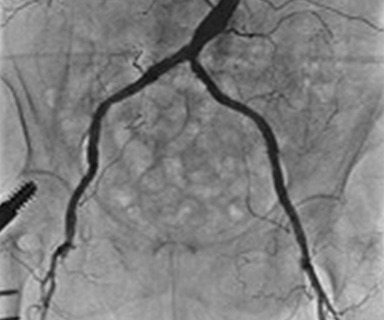

腹部血管造影検査

腹部には様々な動脈・静脈があります。代表的なものとして肝臓の腫瘍に対する検査・治療があげられます。

肝臓は人体の臓器の中で最も大きな臓器(約800~1200g)です。ここには多種類の悪性腫瘍が生じます。大きく分けて原発性肝腫瘍(肝細胞癌:約90%)、転移性肝腫瘍(多臓器からの転移した腫瘍)があります。ここでは原発性肝腫瘍の中でも最も発生が多い肝細胞癌に対する検査・治療をご紹介します。

正常な肝臓は主に門脈と呼ばれる静脈から栄養を補います。しかし肝細胞癌は主に肝動脈から栄養を補います。

門脈は主に胃・小腸・大腸・脾臓などからの静脈が集まって肝臓へ流入します。この静脈は肝臓を通り、肝静脈から下大静脈へ、そして心臓へと流入します。

カテーテル操作をしやすい太い動脈(主に足の付け根)へ麻酔をし、そこからカテーテルを入れます。この検査では門脈の血流状態、肝細胞癌へ栄養を送る動脈を調べます。

検査のほかにもカテーテルから抗がん剤を肝細胞癌へ注入し、栄養を送る細かい動脈の血流を遮断して治療することもできます。これを経カテーテル動脈化学療法塞栓術(TACE:transcatheter arterial chemoenbolization)と呼ばれます。

左側の画像は上腸間膜動脈と呼ばれる小腸や大腸の一部へ流入する動脈を造影して時間をおいて撮影し、門脈の血流を調べています。造影剤を血管内に注入すると目的の血管が黒く映ります。また肝細胞癌は肝動脈から多くの血流を取り込むため黒く染まってきます。治療前の撮影では赤丸の部分にうっすら黒い部分が肝細胞癌です。治療後の撮影では赤丸の部分に黒い部分がなくなっています。